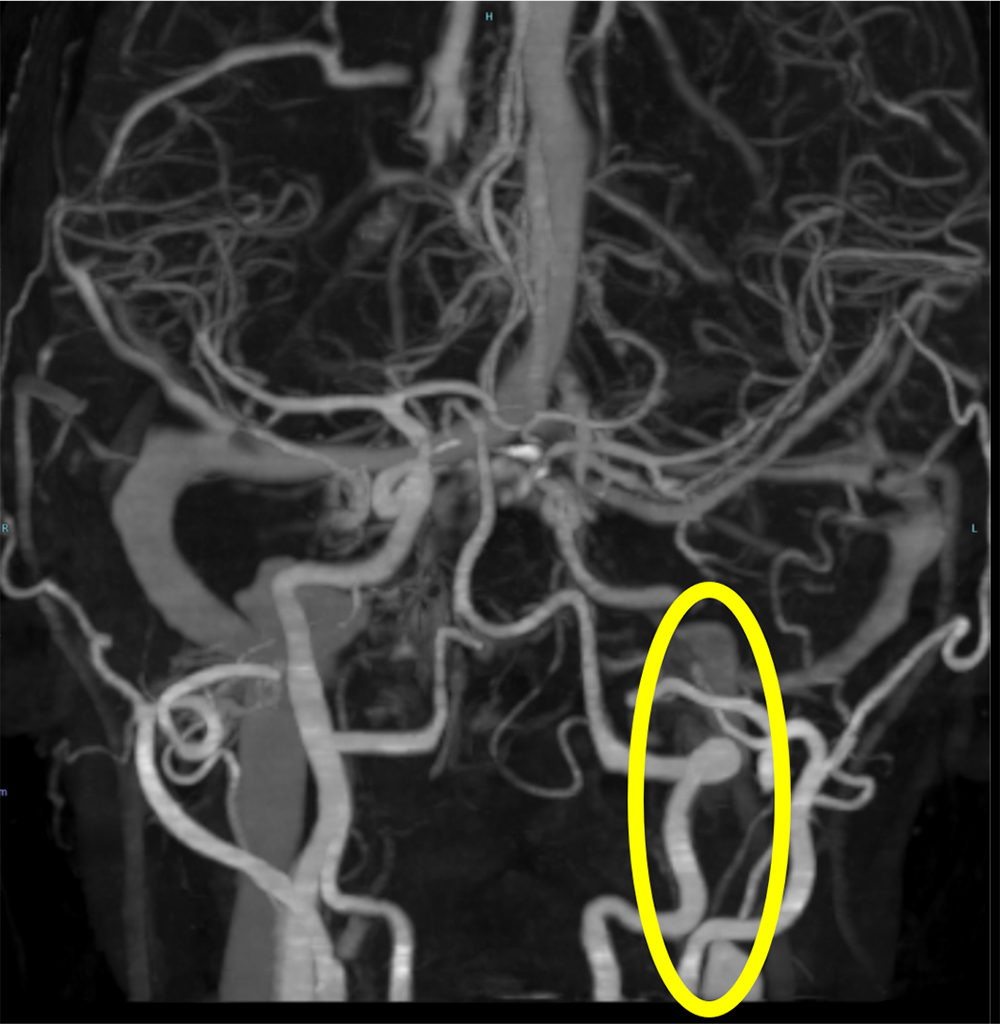

交通外傷後に構音障害が持続し、脳梗塞と診断された患者。内頸動脈解離による閉塞が疑われ、造影CTが施行された。造影CTで左内頸動脈の閉塞を指摘、原因として解離が疑われた。

また、茎状突起の過長はないが、解離部近傍に茎状突起先端が近接しており、茎状突起による内頸動脈解離が疑われたため、茎状突起切除術後に狭窄部ステント留置となった。

術後フォローでは新規梗塞は指摘できず、血流良好であり、10日後に退院となった。

評価手段として血管造影検査が推奨されていたが、最近では細分解能CTも同等の感度があるとされている。

エコー検査も推奨されるが、エコー検査で陰性であってもMRAまたはCTAでの確認が必要とされている。